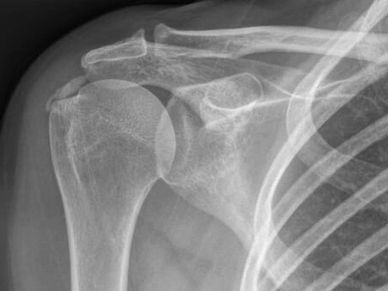

Understand the importance of specific plain films and know the limitations and uses of shoulder imaging.

What to look for on MRI, how to interpret clinically and when US / CT or other specialty imaging is needed.

Diagnostic Imaging